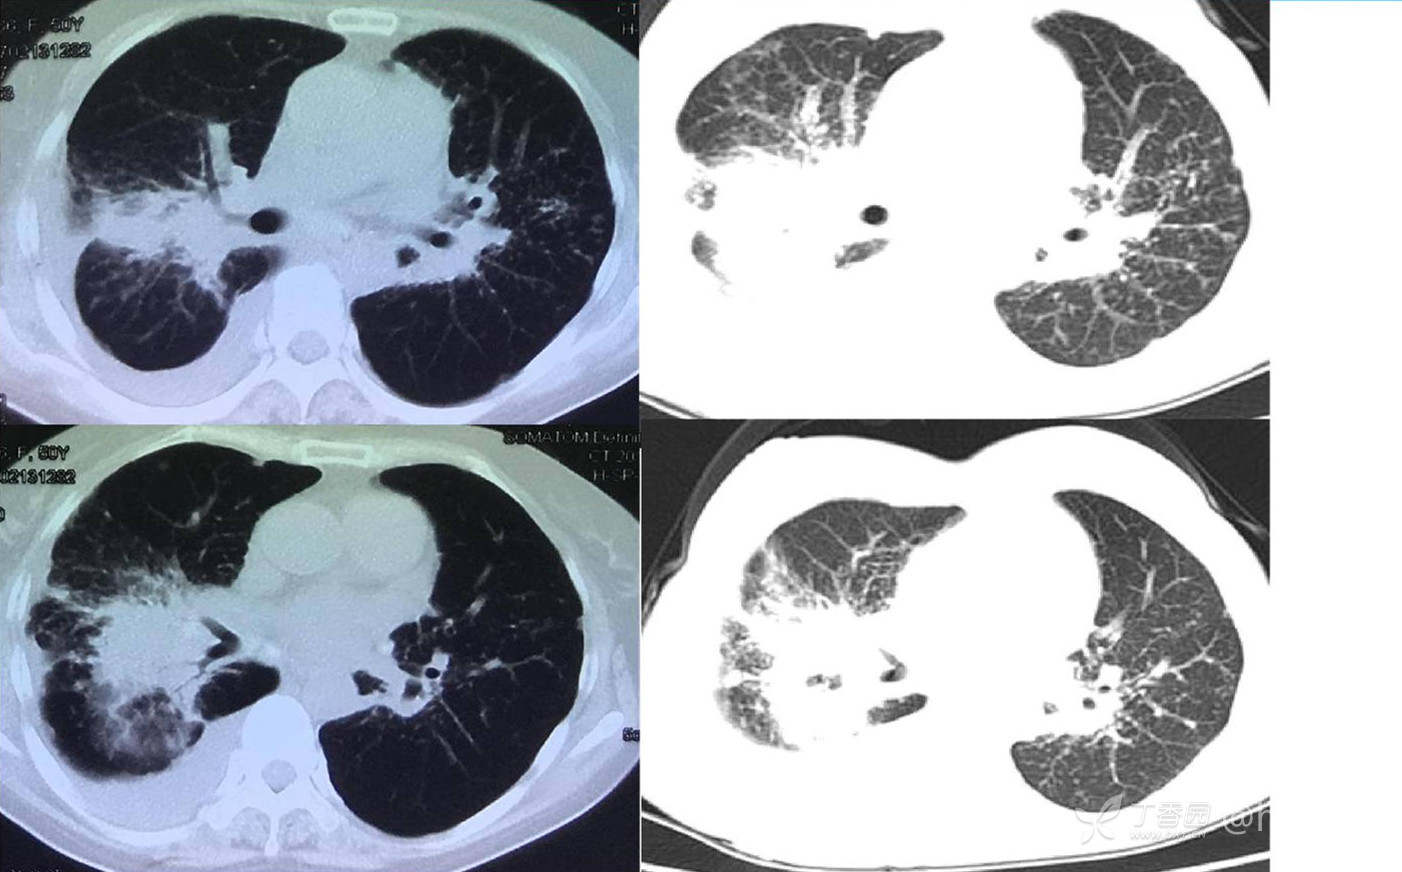

次年行CT复查,病灶进展

增强

临床诊断:双肺弥漫性病变